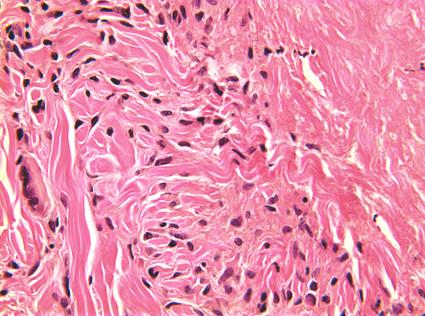

栅栏样模式:特征为真皮中上层淋巴组织细胞炎性浸润,而炎性浸润呈栅栏样包绕胶原及弹性蛋白变性区域。胶原变性区域表现为嗜酸性纤维物质被嗜碱性黏蛋白沉积物所分隔。也可能存在嗜酸性粒细胞。

图:大面积的坏死。该区域被组织细胞和淋巴细胞的外围边缘以及一些多核巨细胞包围。真皮的相邻区域显示正常的胶原束和成纤维细胞核 (HE 40x).